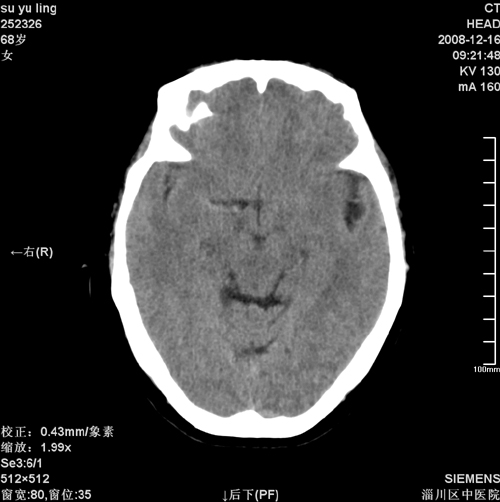

女,68岁,左侧肢体活动不利。

病灶比较均匀钙化,水肿明显,紧贴颅顶与大脑镰并跨越大脑镰----支持脑膜瘤

1)考虑镰旁脑膜瘤钙化。2)小脑萎缩。